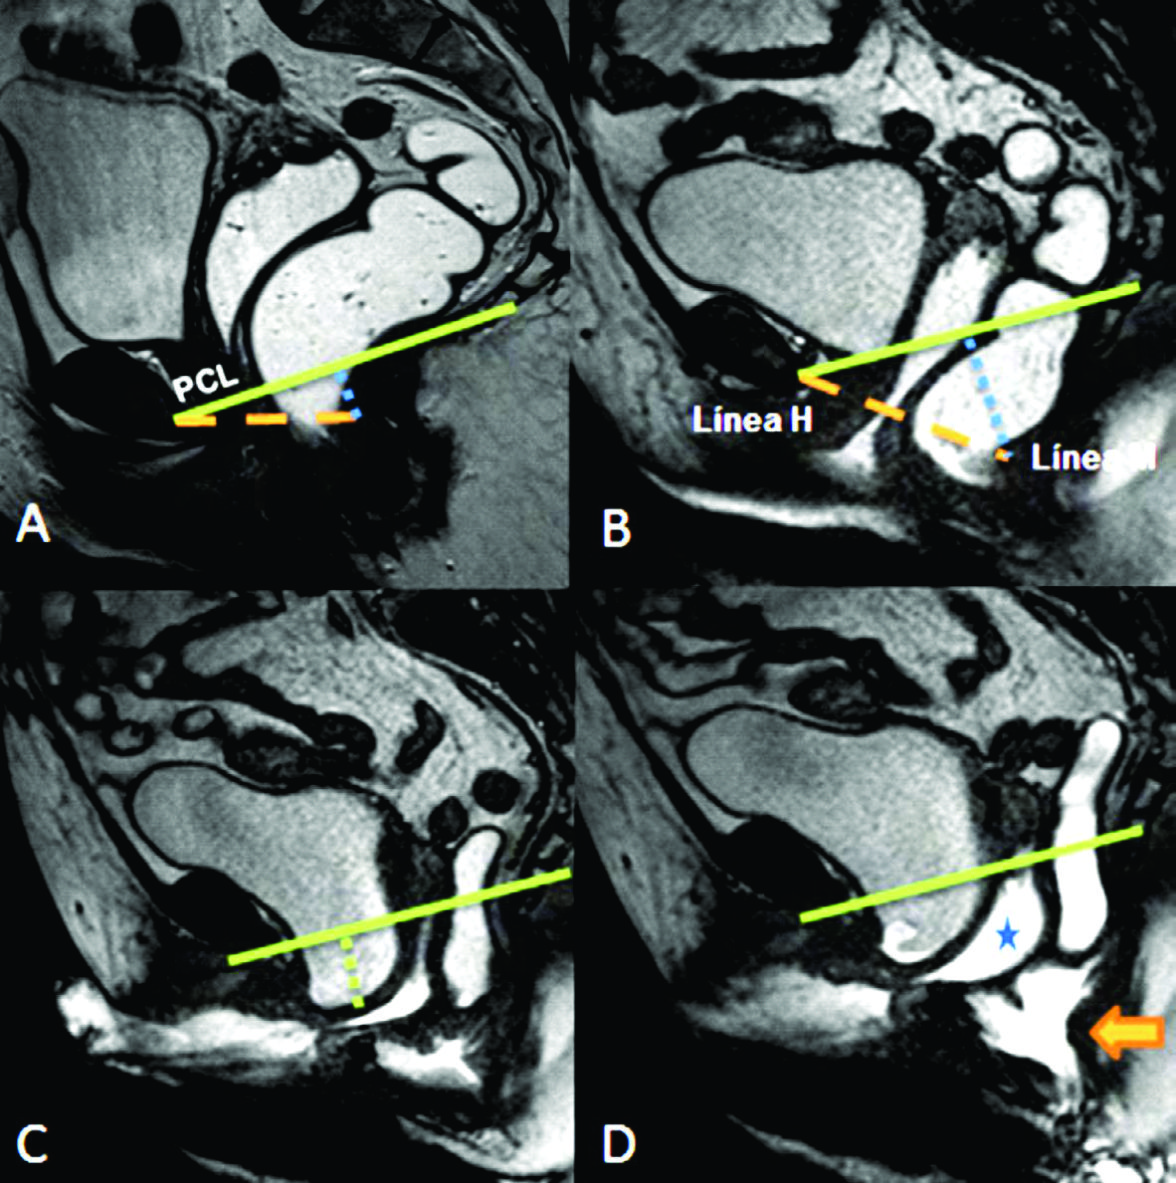

Figura 12

Prolapso multicompartimental

TRUE FISP de alta resolución en el plano sagital durante Valsalva. Existe prolapso de los tres compartimentos. En azul se muestra el eje de la uretra, el cual se encuentra rotado en el plano horizontal, generando hipermotilidad ureteral.

Figura 13

A) Imágenes potenciadas en T2 de alta resolución en el plano sagital. B) TRUE FISP sagital durante defecación. Se identifica cistocele, prolapso de la cúpula vaginal, prolapso uterino y rectocele anterior tanto en el reposo como durante las maniobras dinámicas. Véase herniación de grasa mesentérica (azul en B).

Figura 11

A) Imágenes potenciadas en T2 de alta resolución en el plano sagital. En azul se muestra el eje de la uretra, el cual se encuentra rotado en el plano horizontal, generando hipermotilidad uretral.

B) TRUE FISP sagital durante maniobra de Valsalva. Se identifica cistocele, prolapso de la cúpula vaginal y rectocele anterior.

Los diagnósticos realizados fueron los de cistocele e hipermotilidad de uretra en el compartimento anterior (Ver figuras 6 y 7), histerocele y prolapso vaginal en el compartimento medio (Ver figuras 5, 6, 11 y 13) y sigmoidocele, Douglascele, rectocele y anismo, en el compartimento posterior (Ver figuras 7, 8, 9, 10 y 14).

Aunque todas las mujeres fueron instruidas en realizar contracciones musculares del piso pélvico, una mujer utilizo principalmente músculos abdominales y glúteos durante la contracción voluntaria no pudiendo completar el estudio. El grado de prolapso en la mayoría de los casos fue leve, pero se detectó prolapso en los tres compartimentos (Ver figuras 11, 12 y 13).